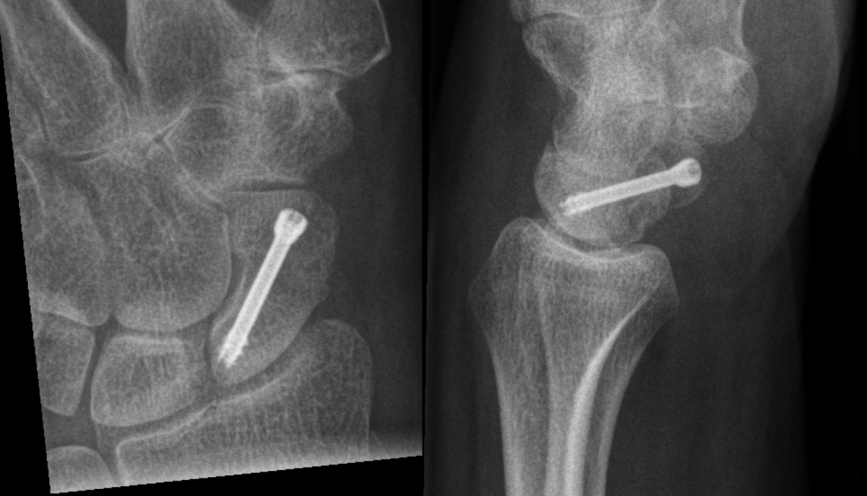

The mean time between trauma and surgery was 10 days. Two cases were treated with an antegrade whereas nineteen with a retrograde approach. For the both methods, a longitudinal incision less than 1 cm was required and reduction aided through the use of a fluoroscope. After blunt dissection was performed to the level of the scaphoid, a guide wire was carefully inserted under fluoroscopic control. The screw length was measured and a cannulated reamer was inserted over the wire. The drilling did not proceed beyond the cortex of the proximal scaphoid pole. The reamer was then removed and a 3.0 mm diameter HCS screw of the appropriate length was inserted. The screw head was still locked by the compression sleeve. When the compression sleeve contacted the proximal pole, the distal thread of the screw engaged the proximal scaphoid fragment and compressed the proximal and distal fragments. The compression sleeve was then retracted and the head of the screw securely seated. The screw position was verified through fluoroscopic methods (Figure 1 [Fig. 1]). A short-arm thumb-spica cast was applied postoperatively allowing unrestricted thumb interphalangeal motion while maintaining the wrist in slight extension. Cast immobilisation was discontinued after 14 days and converted to a removeable splint. Active range-of-motion exercises were encouraged at 6 weeks. Full weight-bearing was allowed after 12 weeks.

Figure 1: A.p. and lateral radiographs after insertion of the Headless Compression Screw